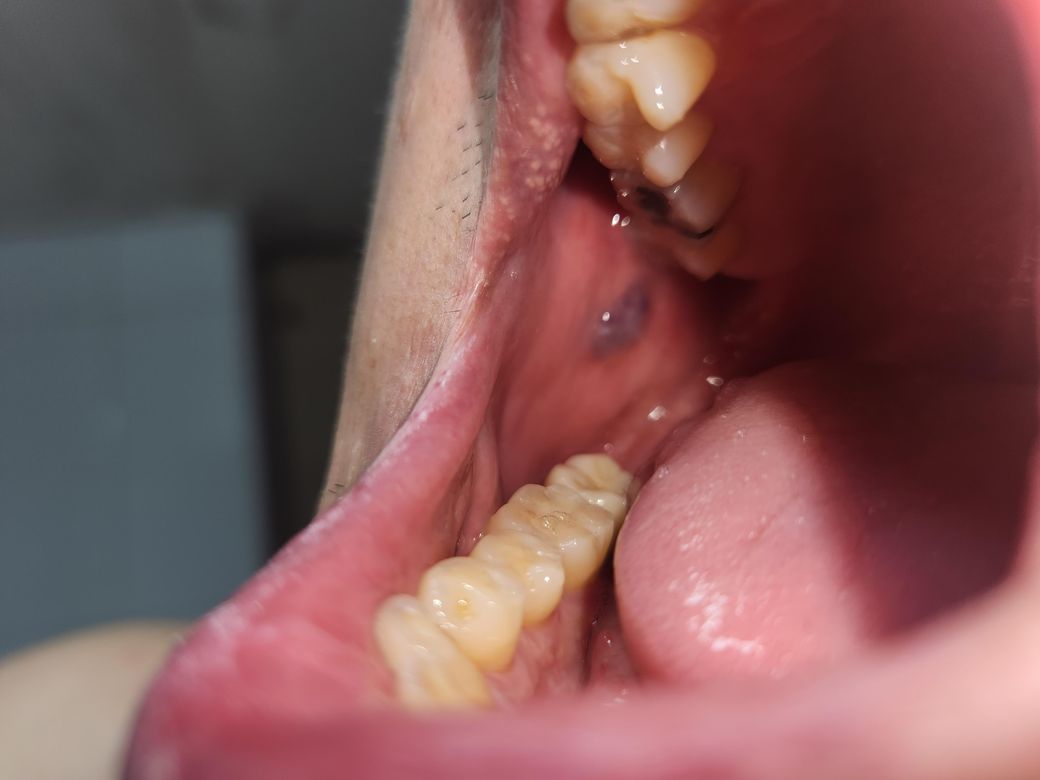

입속에 속으로 검게 변한 흔적이 있습니다.

양치하면서 우연치 않게 발견한 검은 이 반점같은거 무엇인지 궁금 합니다. 치과에 가서 문의하면 되는건가요?? 2두달전 치과도 다녀왔는데 선생님께선 별 말씀 없으셨는데 이게 왜생긴 걸까요??

입안의 검은점이 흡연에 의한 색소침착이거나 외상에 의한 반점일수 있습니다. 만약 해당부위가 지속적으로 없어지지 않고, 남아있는 경우에는 치과진료를 받아보길 권합니다.

정확한 것은 조직검사가 필요하겠습니다만 아마도 볼살을 씹으면서 생긴 혈종이 의심됩니다.

저부위는 볼살이 치아에 씹히면서 안쪽에 피가 고여 잇는거 같습니다. 큰 문제가 잇는건 아니니 너무 걱정하지마세요.

사진으로 보이는 것은 혈종입니다. 점막이 과도한 자극으로 인해서 점막 내부에 출혈이 되면 혈액이 내부에 차게 된서 생긴 혈종입니다.

시간이 지나면서 자연스럽게 없어지게 되며 걱정이 되신다면 치과에서 제거를 할 수 있습니다.